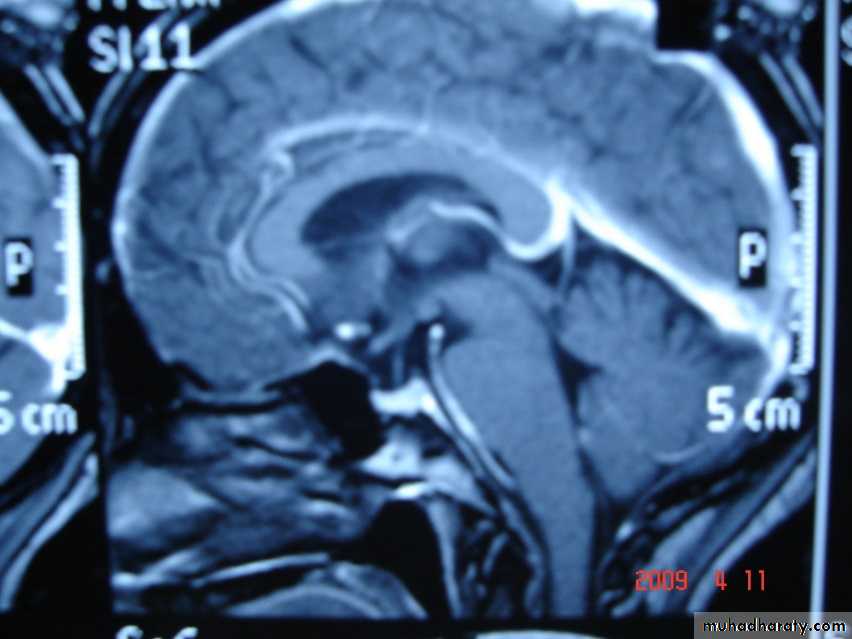

Sagital section of brain ( T1 w post contrast injection)

Coronal T1-weighted MRI image through a brain lesion showing homogeneity of the lesion, lack of a perceptible wall, lack of internal complexity, and CSF signal intensity. There is associated remodeling of the adjacent calvarium and brain displacement. These imaging features are typical of an arachnoid cyst.

Sagittal fluid-attenuated inversion recovery (FLAIR) weighted image through a brain lesion), showing homogeneity of the lesion, lack of a perceptible wall, lack of internal complexity, and CSF signal intensity. There is associated brain displacement. These imaging features are typical of an arachnoid cyst.